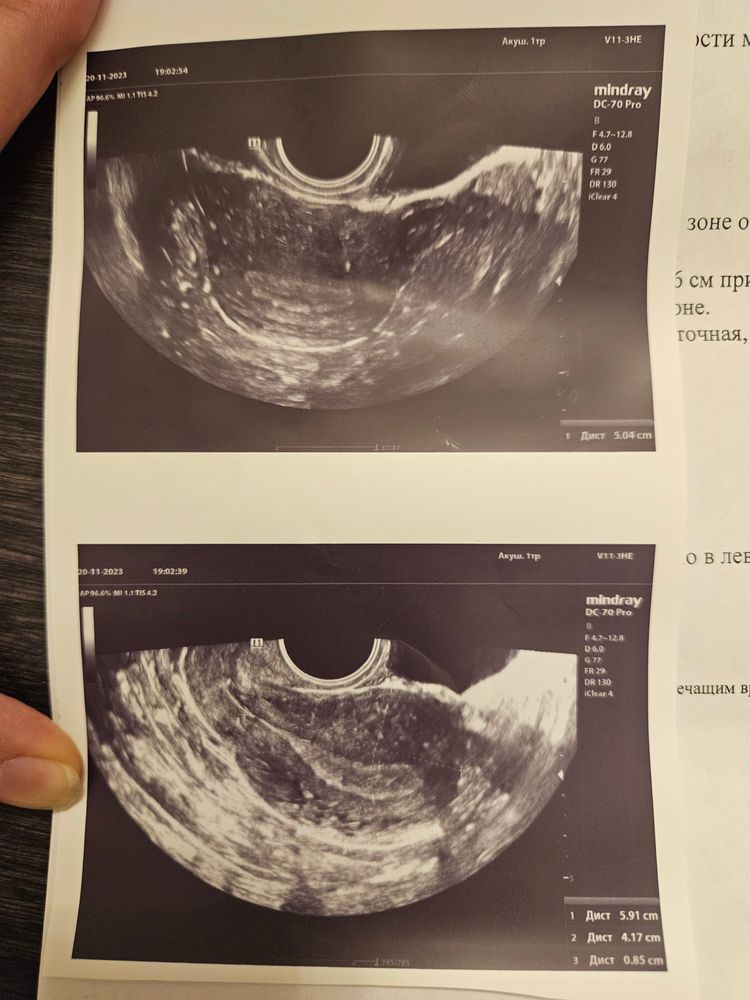

Возможно внематочная, или снова выкидыш

Ольчик, жду утра чтобы получить результат хгч. Коленки трясутся. Надеялась пойти в первый раз на узи в 7 недель. А тут вдруг кровить начало. И до сих пор кровит, а узист ничего в матке не увидела

К сожалению, похоже на вб. У меня всё так же было. Тесты шикарно ярчали (хгч не сдавали), на 6ой неделе даже ПЯ нашли в матке на платном УЗИ (позже стало ясно, что абсолютно не грамотный узист принял миому за пя), а на 7ой неделе начало мазать коричневым, неделю я на дюфастоне сохраняла беременность, а потом ЖК нормальный узиск нашёл эмбрион с сердцебиением в трубе. При вб именно коричневые выделения. Но я очень надеюсь, что этотне ваш случай и всё будет хорошо. Верить надо до последнего И ещё лучше сходит на УЗИ и попросить поискать именно в трубах. Если не затянуть, то трубу можно спасти. Я не успела

Лесенька, пришел анализ хгч 664, маловато для срока, кровить перестало. Хотя перед сном вышла слизь с красными прожилками. Узист искала по трубам не нашла. 😰 в среду иду снова к другому узисту и гинекологу.

Если у вас зачатие было 28,то сейчас 23 дпо,на такое дпо при нормальном росте хгч уже хгч пару тысяч и пя на УЗИ видно,в две беременности отслеживала овуляцию и оба раза ходила на УЗИ на 22 дпо,в одну пя 7 мм было,в другую 8 мм и жм 1,6,если меньше 800,то это не срок маленький,это значит хгч плохо растет,на 23 дпо хгч 800 это очень мало

Марина, вот пришёл анализ хгч. Всего 664 😰

Алыча, мало очень,ещё раз сдайте может и падает уже